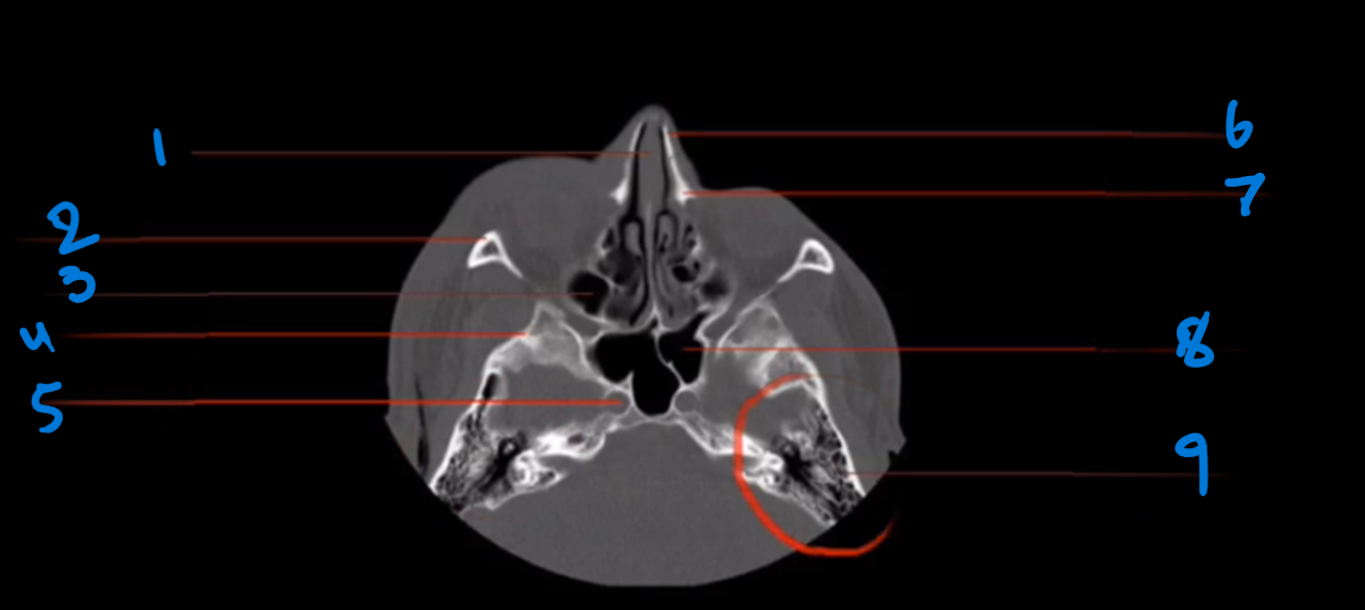

Landmark # 1

Tooth Root

Landmark 2

Mandible

Landmark 3?

Styloid Process, Temporal Bone

Landmark 4?

Anterior Arch, C-1

Landmark 5 ?

Odontoid Process, C-2

Landmark 6 ?

Hard palate, Maxillary bone

Landmark 7?

Hard Palate, Palatine Bone

Landmark 8?

Lateral Mass, C-1

Landmark 9

Posterior Arch, C-1